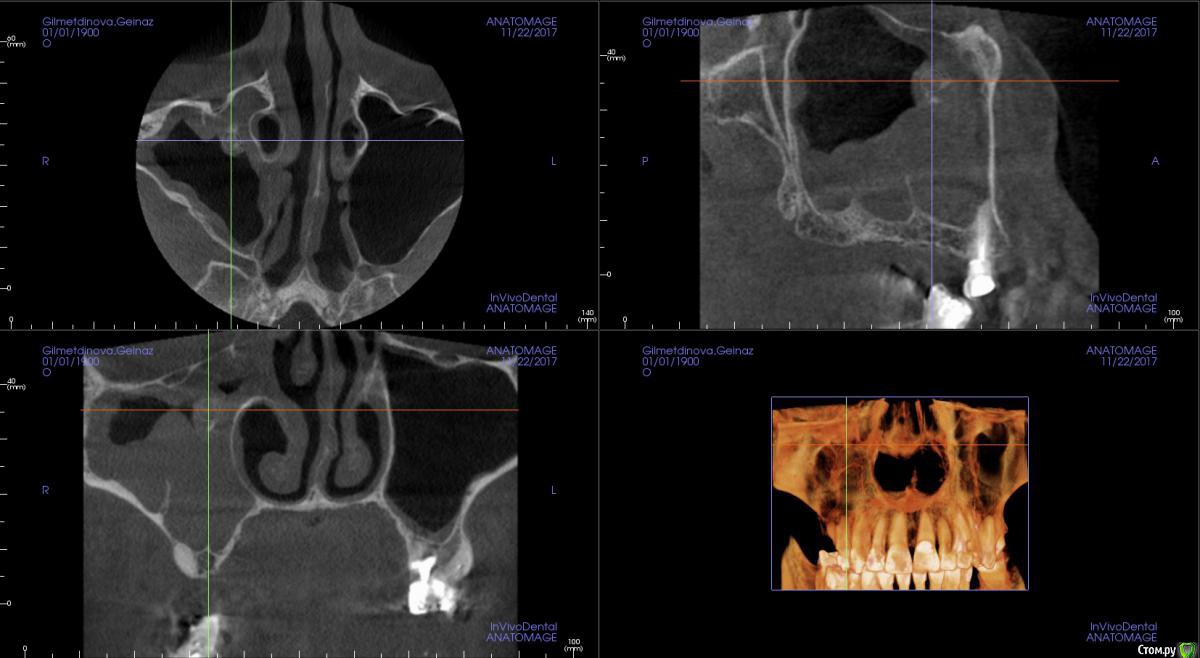

kamranchick Опубликовано 16 апреля, 2018 Автор Поделиться Опубликовано 16 апреля, 2018 Смотрел, и такое заключение дал. вот меня и смутило, в верхней трети около соустя вообще вкрапления какие то есть )) Ссылка на комментарий

Irouil Опубликовано 16 апреля, 2018 Поделиться Опубликовано 16 апреля, 2018 Смотрел, и такое заключение дал. вот меня и смутило, в верхней трети около соустя вообще вкрапления какие то есть ))Больше всего похоже на грибковое тело, и вкрапления эти намекают, и контуры затенения. Пунктировать не стал ЛОР это? 1 Ссылка на комментарий

kamranchick Опубликовано 16 апреля, 2018 Автор Поделиться Опубликовано 16 апреля, 2018 Больше всего похоже на грибковое тело, и вкрапления эти намекают, и контуры затенения. Пунктировать не стал ЛОР этоОтправил для санации, он написал вот это только( что ретенционная, но потом я внимательно начал крутить туда сюда и вот засомневался Ссылка на комментарий

Irouil Опубликовано 16 апреля, 2018 Поделиться Опубликовано 16 апреля, 2018 По большому счету; какая разница то? Вы же пациентку ради синус лифта (насколько я понимаю) отправляли, в таких условиях его не сделать. Там даже если соустье толщиною с пенис Трампа будет, все равно его ткани+отек перекроют после синуса. Так или иначе пазуху надо оперировать, только если ЛОР не считает что ретенционная киста - одонтогенная и пройдет при санации первичного очага) Ссылка на комментарий